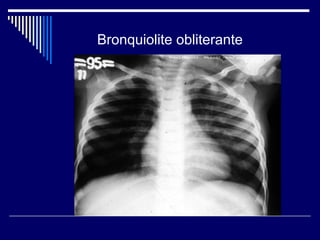

Diagnóstico Diferencial

Bronquiolite obliterante